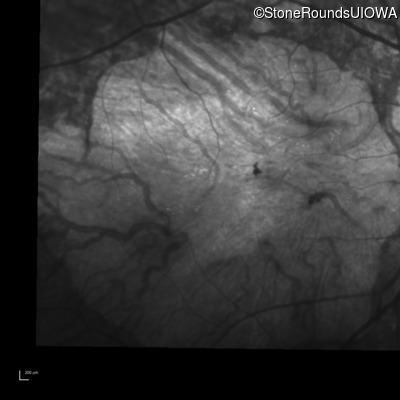

Infrared Fundus Photograph - Right - Unable to Quantify

Exemplar